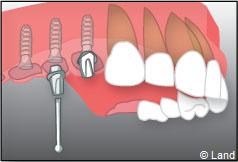

Le chirurgien-dentiste après une anesthésie locale pratique une incision, puis il décolle la gencive pour accéder à l’os alvéolaire.

Ensuite il prépare l’emplacement de l’implant dans l’os en passant plusieurs forets de diamètre croissant. Le forage de l’os se fait à vitesse maîtrisée et lente sous irrigation, pour respecter la structure osseuse et éviter tout échauffement de celle-ci. Le praticien arrête lorsqu’il a obtenu un puits d’un diamètre très légèrement inférieur à l’implant à poser.

L’implant est placé dans l’os le plus souvent par vissage et doit avoir une liaison forte avec l’os. Le praticien replace alors la gencive et pose des points de suture.